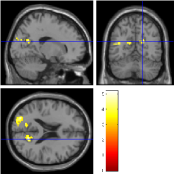

Once the reduced FOV images are available, the proposed pMRI 4D-UWR-SENSE algorithm and its early UWR-SENSE version have been utilized in a final step to reconstruct the full FOV EPI images and compared to the mSENSE Siemens solution. For the wavelet-based regularization, dyadic Symmlet orthonormal wavelet bases [48] associated with filters of length 8 have been used over resolution levels. The reconstructed EPI images then enter in our fMRI study in order to measure the impact of the reconstruction method choice on brain activity detection. Note also that the proposed reconstruction algorithm requires the estimation of the coil sensitivity maps (matrix in Eq. (2)). As proposed in [4], the latter were estimated by dividing the coil-specific images by the module of the Sum Of Squares (SOS) images, which are computed from the specific acquisition of the -space centre (24 lines) before the scans. The same sensitivity map estimation is then used for all the compared methods. Fig. 5 compares the two pMRI reconstruction algorithms to illustrate on axial, coronal and sagittal EPI slices how the mSENSE reconstruction artifacts have been removed using the 4D-UWR-SENSE approach. Reconstructed mSENSE images actually present large artifacts located both at the centre and boundaries of the brain in sensory and cognitive regions (temporal lobes, frontal and motor cortices, …). This results in SNR loss and thus may have a dramatic impact for activation detection in these brain regions. Note that these conclusions are reproducible across subjects although the artifacts may appear on different slices (see red circles in Fig. 5). One can also notice that some residual artifacts still exist in the reconstructed images with our pipeline especially for . Such strong artifacts are only attenuated and not fully removed because of the high level of information loss at .

| mSENSE | 4D-UWR-SENSE | ||

| Axial |  |

|

|

| Coronal | |||

| Sagittal | |||

| Axial |  |

|

|

| Coronal | |||

| Sagittal |